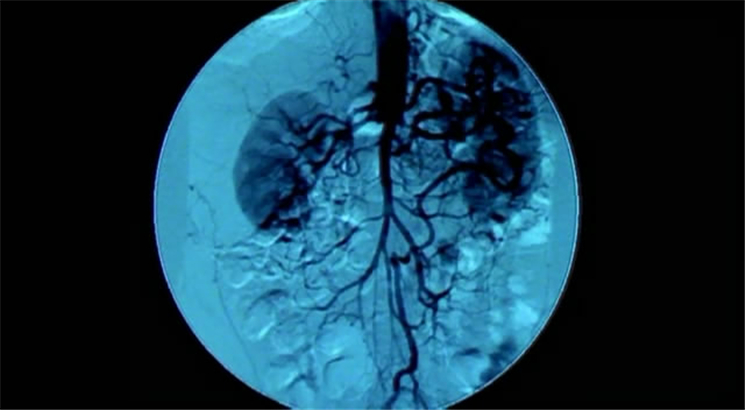

1.创伤医学

「剑伤医学」发掘人体在车祸等严重创伤后,如何激发潜藏体内的自我复元能力。崭新的创伤医学意味着未来人类在严重创伤中…